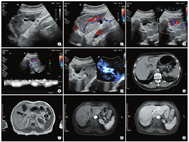

患者女,75岁,主因糖尿病入院治疗。无肝炎、外伤及肝部手术病史。既往超声检查诊断肝左叶囊肿。入院后常规超声检查:肝左外侧叶可见范围约4.9 cm×3.3 cm×2.4 cm的囊性回声,形态不规则(图1),门静脉左支及肝左静脉内径增宽,囊状结构与矢状部关系密切。彩色多普勒血流显像(CDFI)示:囊性回声内可见红蓝相间的涡流信号,与门静脉左支相延续(图2),并可见一通道与肝左静脉内侧支相通(图3),通道内为蓝色为主的花彩血流信号,流速约50 cm/s(图4)。微血管显像显示此囊性回声内血流分别与门静脉左支、肝左静脉内侧支相通(图5)。另可见肝左叶及尾状叶相对增大,下腔静脉肝后段内径变细约0.2 cm(其近心端内径1.2 cm,其远心端内径1.3 cm)。CDFI示:血流束变细,血流速度增快约154 cm/s。超声提示:肝左叶内囊性回声,考虑门静脉瘤,门-体分流不除外;下腔静脉肝后段受压。上腹部CT检查:肝左叶类圆形稍低密度影,边界清(图6)。后行上腹部MRI及增强检查示:肝左叶外侧段可见类圆形异常信号影,大小约4.5 cm×2.8 cm×3.0 cm,呈不均长T1长T2信号,DWI呈低信号(图7)。注射增强剂后动脉期略有增强(图8),门静脉期示迂曲增粗血管影,强化幅度与门静脉相仿(图9),平衡期与肝左静脉沟通汇入下腔静脉。提示:肝左叶异常影,考虑门体分流,门静脉瘤形成。

本例患者通过超声检查首先发现位于肝左外叶下段有一囊性回声,CDFI显示其内为红蓝相间的湍流信号,否定了此前囊肿的诊断。后通过实时二维、彩色血流及微血流显像技术判断此囊性回声内血流来源于门静脉左支,同时发现瘤体通过一通道与肝左静脉内侧支相通。进一步通过二维超声观察到患者门静脉矢状部结构不完整,左支较右支内径增宽,肝左静脉内径较肝中静脉、肝右静脉内径增宽,下腔静脉局部内径变细,血流速度增快,造成下腔静脉狭窄的原因考虑是由于肝静脉内血流量加大,引起继发性肝左叶及尾状叶淤血,体积相对增大造成的,这一点需要临床进一步证实。